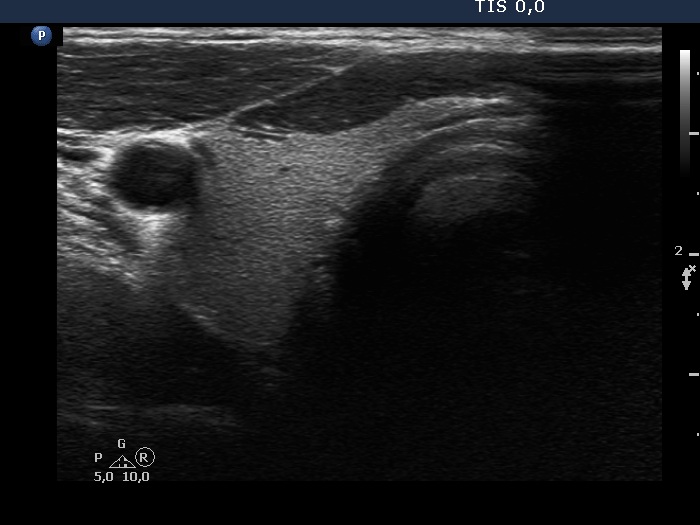

The shape of the nodule - case 1370 |

Clinical data: A 45-yr-old man was referred for aspiration cytology of a nodule discovered by carotid Doppler examination.

Ultrasonography. The thyroid was echonormal. Both lobes presented nonparallel orientation. There was a minimally-moderately hypoechoic nodule in the left lobe. The nodule showed taller-than-wide shape and signs of perinodular blood flow.

Cytology resulted in benign colloid goiter.

Comment. It is very hard to imagine how could a nodule not showing nonparallel orientation if it is found in a lobe which itself has nonparallel orientation. In smaller nodules which does not extend to the entire width of the lobe. nonparallel orientation may have some meanings. However, a lesion which extends across the entire width of the lobe, further growth is hindered by anatomical structures. Therefore, such nodules can only continue to grow in the anteroposterior direction.